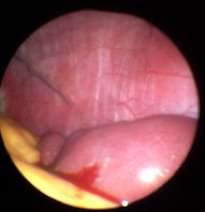

Milzbiopsie bei Sarkoidose